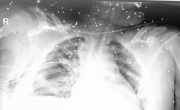

مرآة البحرين: قالت شبكات محلية إن أحد المحتجين في سترة أصيب بإصابة خطيرة، بعدما فتحت قوات النظام الأسلحة النارية على تظاهرات في الجزيرة. وقالت الشبكات إن المحتج أصيب بالرصاص الإنشطاري في وجهه، ووصفت إصابته بـ "الخطيرة".

مرآة البحرين: قال المواطن حسن العجمي إن الوضع الصحي العام لابن أخته الطفل محمد السواد (13 عاماً) قد استقر أمس الاثنين 2 فبراير/ شباط إلا أن هناك قلق كبير بوجود احتمالية من فقدانه لإحدى عينيه بعد أن وصلت شظايا "الشوزن" لها.